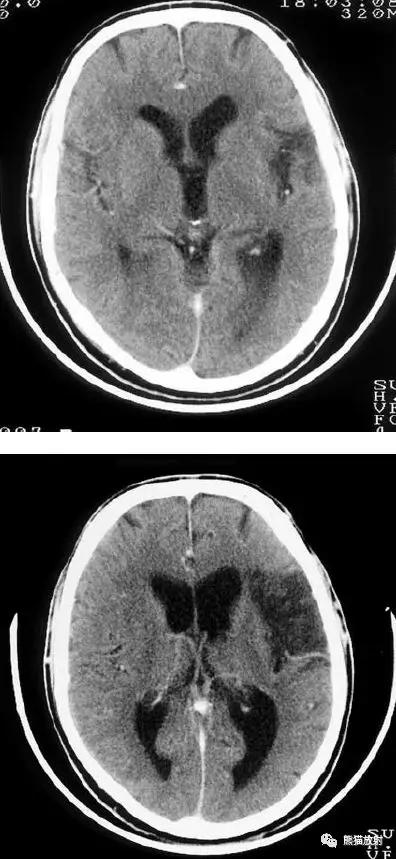

大脑中动脉区梗死:部分梗死,仅累及左侧浅表区域。

左侧大脑中动脉区完全梗死,对邻近的侧脑室产生占位效应;右侧可见其他较小的缺血性低密度区。

右侧大脑前动脉供血区部分梗死

右侧大脑后动脉供血区梗死

双侧大脑后动脉供血区梗死